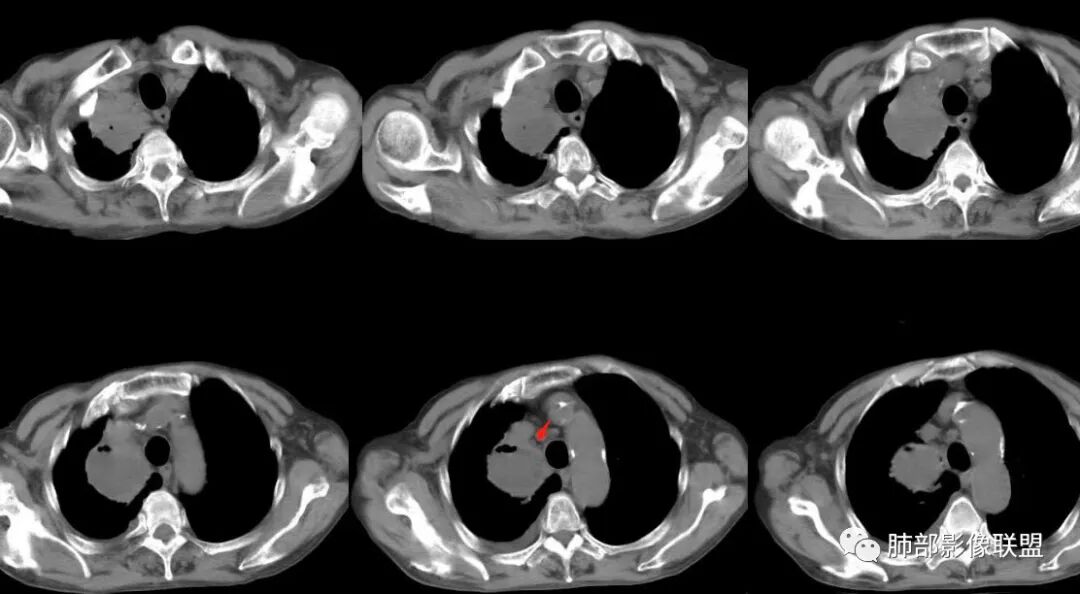

1月后,发热再次入院

这些新发的

合并有胸水

出现液气平面

治疗一周后复查

周围干净了,液平小了

壁似乎均匀了

治疗两周,病灶内气体没了

就目测看内壁还是清楚的